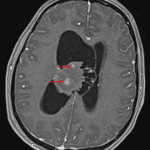

CT with contrast

- Mildly hyperattenuating mass in the body of the right lateral ventricle with cystic components along its medial margin and broad contact with the septum pellucidum

- Patchy internal areas of enhancement